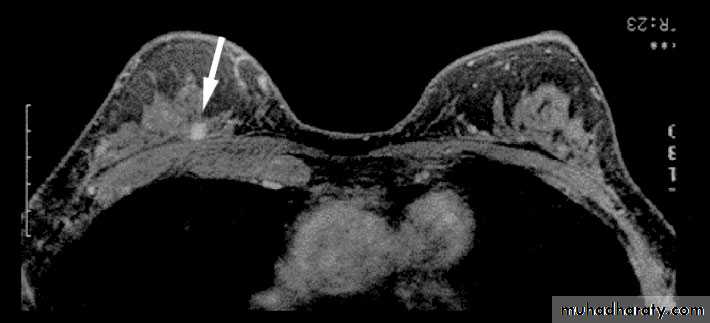

(3)magnetic resonance imaging (MRI); MRI is of increasing interest to breast surgeons in a number of setting: it can distinguish scar from recurrence in women who have had previous breast conservation therapy for cancer. It is the best imaging modality for the breast of women with implants. It has proven to be a useful as screening tool in a high risk women because of a family history. It is less useful than ultrasound in the management of the axilla in both primary breast cancer and recurrent diseases.